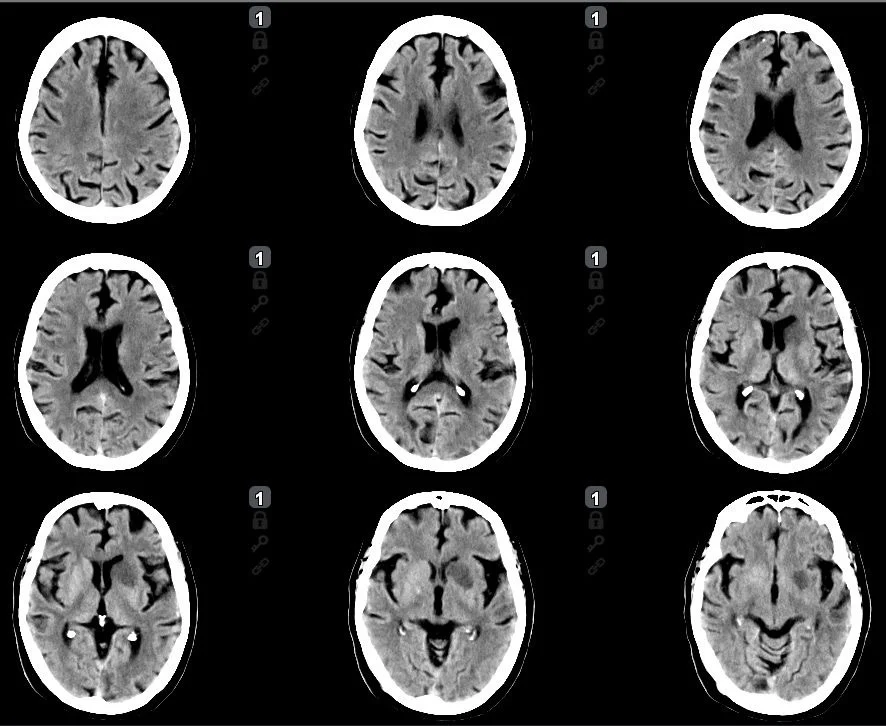

Stroke CT workup showed 16 ml well delignated infarct of the head of caudatenucleus and putamen (ASPECTS 8), a proximal left M1 occlusion and 40 ml of perfusion lesion in the MCA territory (18:25, Brainomix). No thrombolysis.